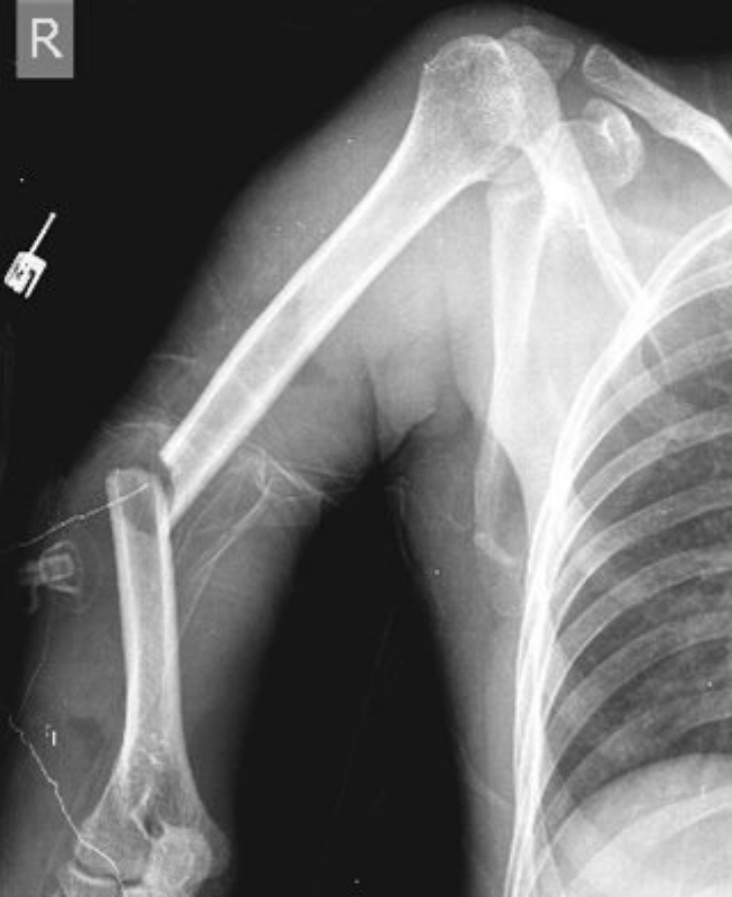

Pogledajte kako izgleda ruka Edina Višće nakon teškog loma!

Pregledom je utvrđeno je da je Višća doživio prijelom nadlaktične kosti. Očekuje se da će bh. igrač biti van terena najmanje dva mjeseca.

Pogledajte kako izgleda njegova ruka nakon teškog loma nadlaktične kosti.